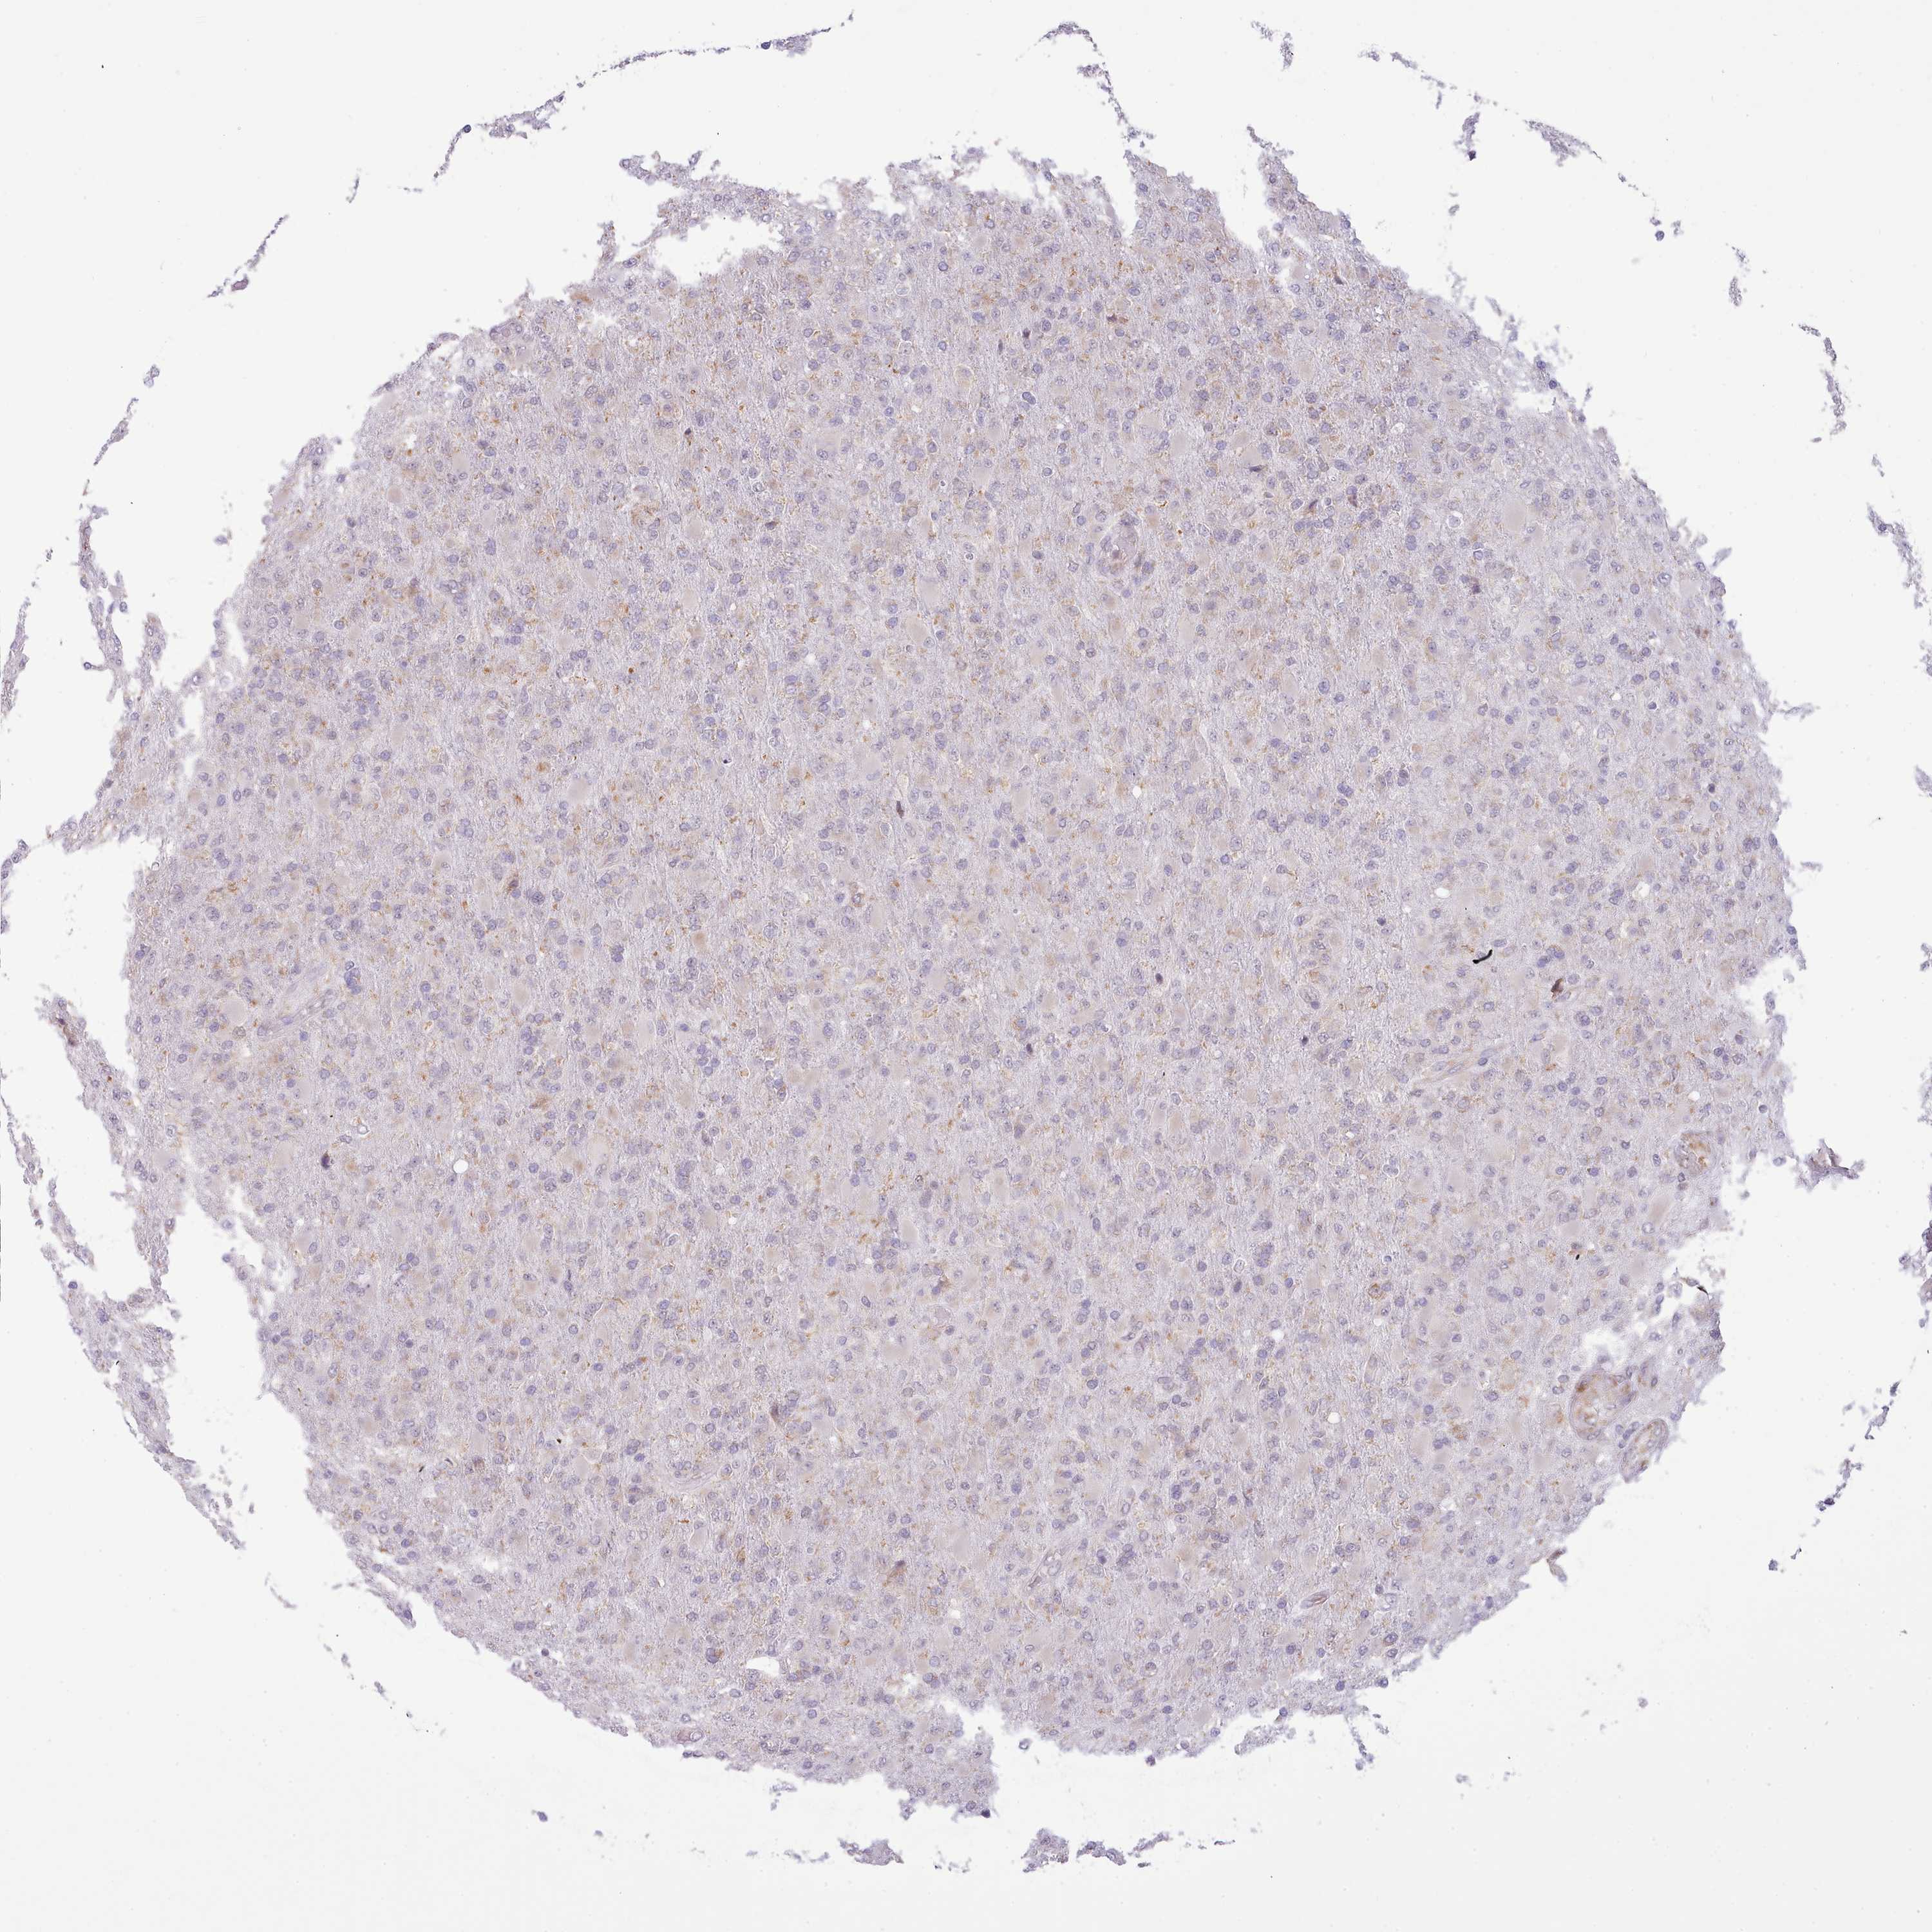

GLIOMA - Protein expressioni

A mouse-over function shows sample information and annotation data. Click on an image to view it in a full screen mode. Samples can be filtered based on level of antibody staining by selecting one or several of the following categories: high, medium, low and not detected. The assay and annotation is described here.

Note that samples used for immunohistochemistry by the Human Protein Atlas do not correspond to samples in the TCGA dataset.

Antibody stainingi

Antibody staining in the annotated cell types in the current human tissue is reported as not detected, low, medium, or high, based on conventional immunohistochemistry profiling in selected tissues. This score is based on the combination of the staining intensity and fraction of stained cells.

Each image is clickable and will lead to virtual microscopy that enables deeper exploration of all samples and also displays staining intensity scores, fraction scores and subcellular localization as well as patient and tissue information for each sample.

Antibody HPA049407

Staining

High

Medium

Low

Not detected

Intensity

Strong

Moderate

Weak

Negative

Quantity

>75%

75%-25%

<25%

None

Location

Nuclear

Cytoplasmic/membranous

Cytoplasmic/membranous,nuclear

Glioma, malignant, High grade

Glioma, malignant, Low grade